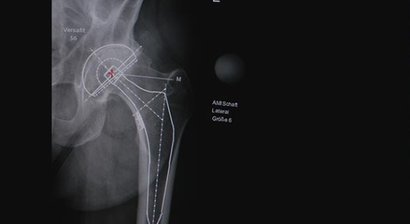

Im Falle einer notwendigen Operation wird diese von mir im Evangelischen Krankenhaus Wien durchgeführt. Meine chirurgischen Schwerpunkte liegen im künstlichen Gelenkersatz , in der Fußchirurgie und den arthroskopischen Operationstechniken.

Ich habe mich auf die Implantation von künstlichen Knie- und Hüftgelenken spezialisiert und setze hier auf monderne minimalinvasive und schonende Operationstechniken (AMIS-Methode).

Künstliches Hüftgelenk (nach der minimal invasiven AMIS-Methode)